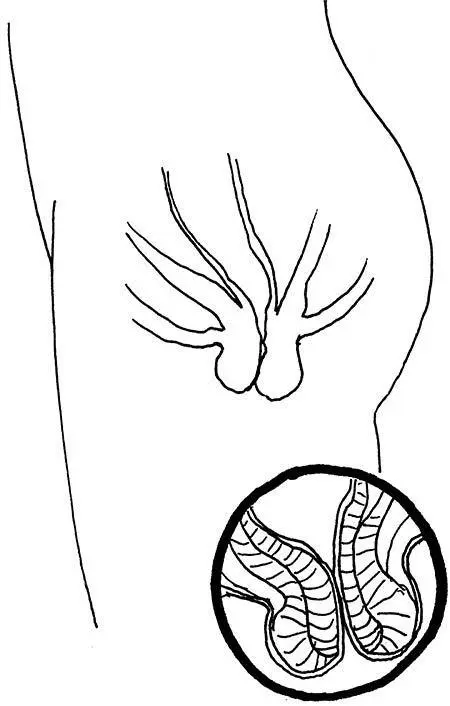

Пролапс – это когда орган выглядывает из того места, откуда не должен выглядывать. Ректальный пролапс, или выпадение прямой кишки, предполагает, что из ануса виднеется часть той самой кишки.

Ректальный пролапс.

Венец вашей системы пищеварения свешивается из анального отверстия. Другими словами, из вас вышли не только каловые массы, но и часть кишечника.

Вы тужитесь – и бух! – органы, которые должны быть внутри вас, выпрыгивают наружу. У молодых и здоровых людей это явление встречается сравнительно редко. Это заболевание поражает пожилых женщин, которые рожали много раз, в результате чего кольцевые мышцы рвались единожды или многократно. Каплей, переполняющей чашу, часто становится запор, когда пациенту приходится прилагать дополнительные усилия при походе в туалет.

Прежде чем рассказать, почему ваша прямая кишка выпадает из ануса, важно дать вам понять, почему обычно она этого не делает. Правильный вопрос, стало быть, звучит так: почему кишки не выходят наружу каждый раз, когда вы тужитесь? что именно удерживает их на месте? Как много раз бывало на страницах этой книги, нужно отдать должное сфинктерам. Они сокращаются и удерживают кишки внутри. Сами же кишки, в сущности, ни к чему не прикреплены: они резвятся и извиваются у вас в животе. Поэтому если анальное отверстие увеличивается в диаметре, например из-за повреждения сфинктеров, они запросто могут выпасть от достаточно сильного давления изнутри.

«Да, но я никогда не давлю на них изнутри», – станете оправдываться вы. А что вы тогда делаете, когда сидите на унитазе и пыхтите? Вы вдыхаете побольше воздуха и давите диафрагмой на кишечник. Напрягаете мышцы живота, чтобы ужать все его содержимое и выдавить лишнее, как икорную пасту из тюбика. На самом деле вы довольно часто пытаетесь выдавить кишечник наружу и должны каждый божий день благодарить кольцевые мышцы вашего ануса за то, что они с вами не согласны.